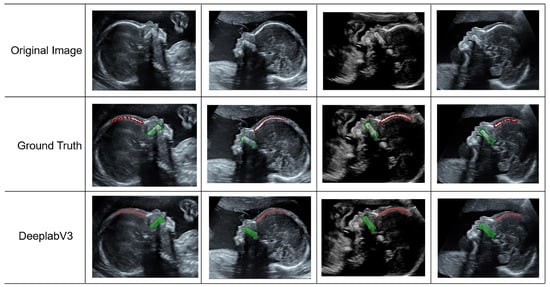

3.1. Evaluation of Segmentation